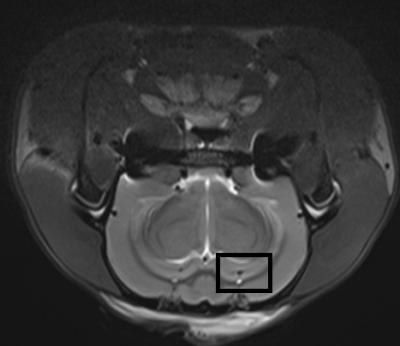

Magnetic resonance spectroscopy can quantitatively analyze in vivo abnormalities of biochemical metabolism within brain tissue in a noninvasive and non-radioactive manner. Compared with 3.0T magnetic resonance spectroscopy, high-field magnetic resonance spectroscopy (≥ 7.0T) exhibits high spatial resolution and density resolution, microscopic imaging of the living body, and obtains both high scanning resolution and result precision within a shorter scan time, thus providing a higher value in clinical diagnosis. In a recent study reported in the Neural Regeneration Research (Vol. 9, No. 4, 2014), 7.0T magnetic resonance spectroscopy showed that in the hippocampus of Alzheimer's disease rats, the N-acetylaspartate wave crest was reduced, and the creatine and choline wave crest was elevated. This finding was further supported by hematoxylin-eosin staining, which showed a loss of hippocampal neurons and more glial cells. Moreover, electron microscopy showed neuronal shrinkage and mitochondrial rupture, and scanning electron microscopy revealed small size hippocampal synaptic vesicles, incomplete synaptic structure, and reduced number. Overall, these findings from Lei Zhang and co-workers from Beijing Tiantan Hospital Affiliated to Capital Medical University in China revealed that 7.0T high-feld nuclear magnetic resonance spectroscopy detected the lesions and functional changes in hippocampal neurons of Alzheimer's disease rats in vivo, allowing the possibility for assessing the success rate and grading of the animal model of Alzheimer's disease.